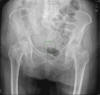

Fractura de cuello de fémur.

Fractura de cuello de fémur